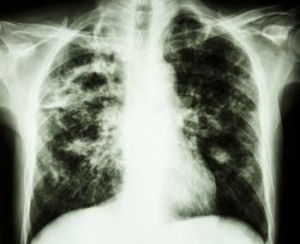

La fibrosis pulmonar es una enfermedad que hace que los pulmones que se tratarán en el tejido de la cicatriz. A medida que la enfermedad progresa, la falta de aliento que acompaña se pone peor.

La enfermedad se puede desarrollar después de la exposición al amianto y el gas tóxico, e incluso el tratamiento de radiación para el cáncer de pulmón. Enfermedades inflamatorias y autoinmunes crónicas también pueden dar lugar a la misma.

Por desgracia, a menudo no se diagnostica hasta que los síntomas aparecen, por lo que ya se ha producido el tiempo cicatrices permanentes.